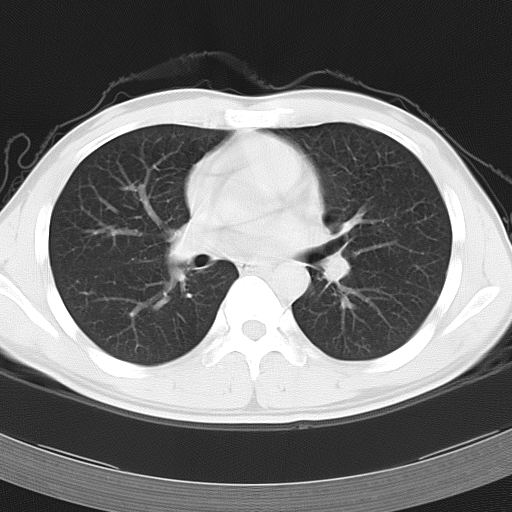

男,34岁,咳嗽2~3个月,无咳血,病初有发热。

病变分布以双上肺叶外带明显,双下肺未见异常,此一点不十分支持肺泡蛋白质沉着症,病变未见铺碎路石征,也不肺泡蛋白质沉着症。考虑间质性肺炎,结核不除外。

据报告﹐自7~8个月的婴儿至72岁的老人均有患肺泡蛋白沉积症者﹐但以30~50岁者居多。男性约为女性的3倍。鉴于约半数病人经常接触各种粉尘或有害气体﹐且以硅尘长期给鼠吸入﹐可使动物患肺泡蛋白沉积症﹐故认为本病可能是肺泡对化学性刺激的非特异性反应,导致肺泡巨噬细胞分解,产生pas阳性蛋白质。

该患者男性,34岁,进一步追问病史,该人系矿砂堆场码头工人,长期粉尘环境下工作。--这条病史符合以上特点。

ct表现 (1)中央型:表现为蝶翼状浸润性阴影对称分布于两侧肺门周围,其内可见支气管充气征,病变区与正常肺组织分界清楚。(2)外围型:表现为多发性条片状、斑片状及斑块状高密度影,弥散、对称或不对称分布于两肺或一侧肺外围部位。病变区与正常肺组织及脏层胸膜面分界清晰,呈地图样改变。hrct可显示小叶间隔增厚及肺小叶内淡淡的密度增高影等细微结构,同时易发现肺大疱、肺气囊及节段性肺不张。

再仔细阅读该病人的ct片,我们不难发现,病例所表现的正是外围型的肺泡蛋白沉积症表现,即:为多发性条片状、斑片状及斑块状高密度影,弥散、对称或不对称分布于两肺或一侧肺外围部位。病变区与正常肺组织及脏层胸膜面分界清晰,呈地图样改变。

所以,我本人的意见也是趋向于肺泡蛋白沉积症的诊断,尽管最后诊断还是要根据支气管肺泡灌洗物检查或经纤支镜或剖胸活检作出病理诊断。或痰液检验:咳出的痰经80%乙醇固定,pas染色有15%阳性的脂质。

该病人经过1周抗炎治疗,病灶基本消退,仅存毛玻璃样改变。

但根据文献记载(http://baike.baidu.com/view/778576.htm),肺泡蛋白沉积症 无特殊治疗﹐60~70%的成人患者可自行恢复。故本人还是觉得该病例自愈的可能性比较大,跟抗炎治疗无直接的关系。